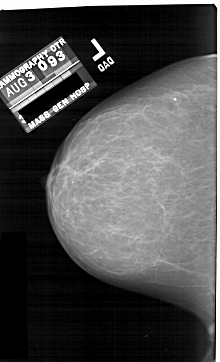

A_1690_1.LEFT_CC

LEFT_CC LINES 6511 PIXELS_PER_LINE 3946 BITS_PER_PIXEL 12 RESOLUTION 43.5 NON_OVERLAY